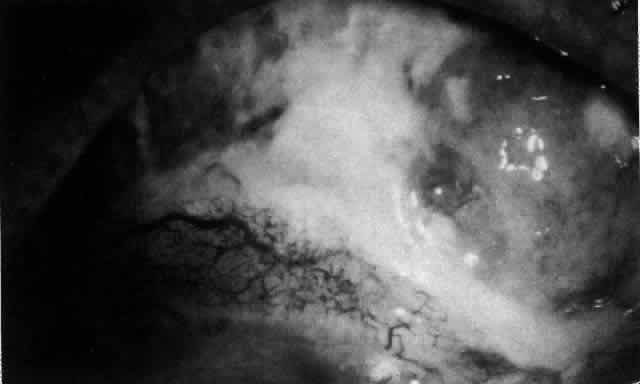

Fig. 41. Late stage of fluorescein angiogram adjacent to the site of necrosis in

the same patient as in Figure 40. Although the eye is uniformly congested, the area near the necrosis shows

vascular shutdown, whereas the rest of the conjunctiva and episclera

is normally perfused. Fig. 41. Late stage of fluorescein angiogram adjacent to the site of necrosis in

the same patient as in Figure 40. Although the eye is uniformly congested, the area near the necrosis shows

vascular shutdown, whereas the rest of the conjunctiva and episclera

is normally perfused.

|